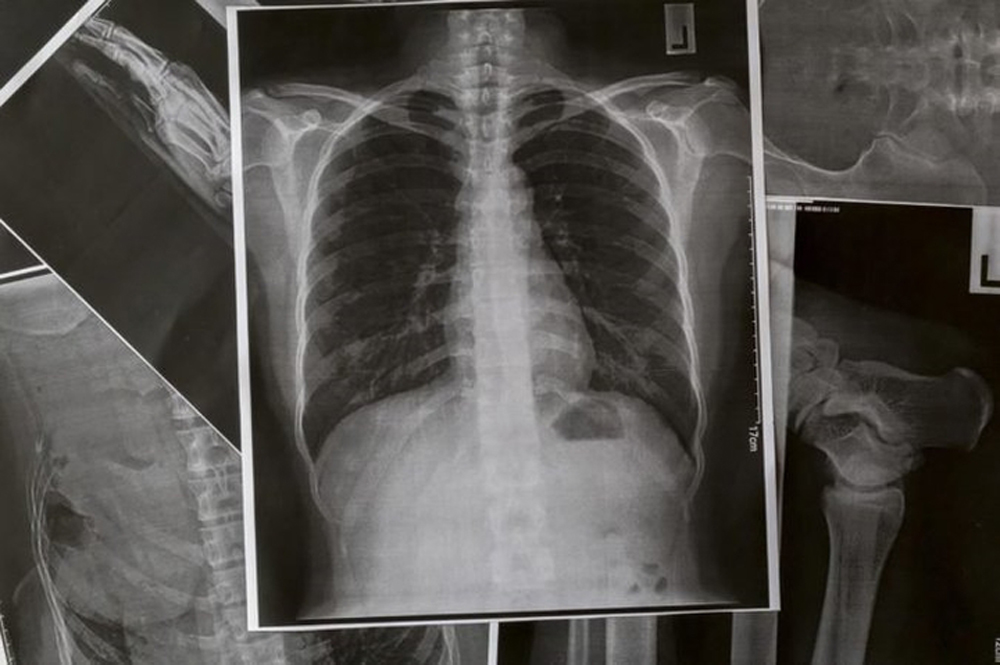

12 dấu hiệu cảnh báo phổi của bạn đang gặp vấn đề